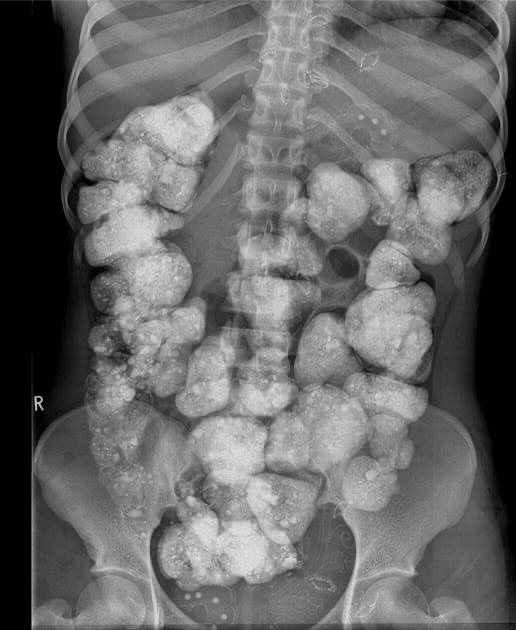

Интересный рентген. Фото: canva

Говорят, рентгеновские лучи невозможно обмануть, но пользователи соцсетей доказали: их можно превратить в настоящий комедийный триллер. Все началось с одного случайного снимка, который за считанные часы разлетелся по сети, превратившись в веральный мем.

Представители самых разных профессий рассмотрели в нем отражение тяжелых рабочих будней, профессиональной деформации и даже ежедневных привычек. Мы собрали вам самые яркие остроумные комментарии, которые заставят вас по-другому взглянуть на обычный снимок, которым поделилась в threads Анастасия Великая.

Анастасия работает врачом рентгенологом и выложила в threads интересный рентген с комментарием. "Супер интересен рентген Ваши догадки?".

На самом деле на картинке случай геофагии – это умышленное употребление земли, почвы или глины. Хотя геофагия может наблюдаться в контексте разных культурных или религиозных традиций, ее также обнаруживают у пациентов с поведенческими расстройствами или психическими заболеваниями.